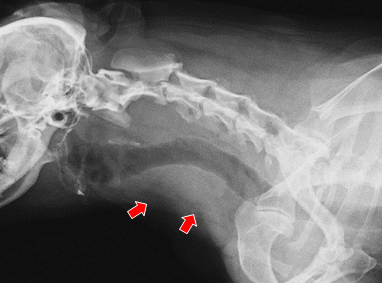

【実施症例】甲状腺癌に対する動注療法

ミニチュア・ダックスフンド、12歳、雌。

周囲組織に浸潤した甲状腺癌で外科的切除は困難であった。 大腿動脈からカテーテルを挿入し、腫瘍栄養血管である甲状腺動脈に抗がん剤と塞栓物質の選択的注入を行った。 実施後、腫瘍は縮小し症状の改善が得られた。

実施前のX線像(腫瘍が気管を圧迫)

実施前のX線像

(腫瘍が気管を圧迫)

実施後のX線像(腫瘍が縮小し気管の圧迫が改善)

実施後のX線像

(腫瘍が縮小し

気管の圧迫が改善)